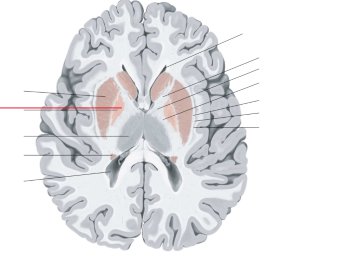

nucleus caudatus

putamen

globus pallidus

capsula interna (corona radiata)

capsula externa

capsula extrema

fornix

laterale ventrikels (I en II)